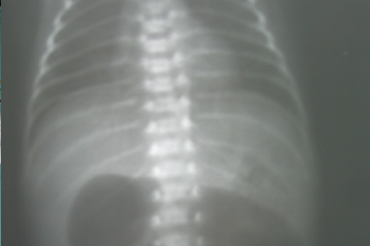

Atresia Intestinal

Neonatal y Lactante